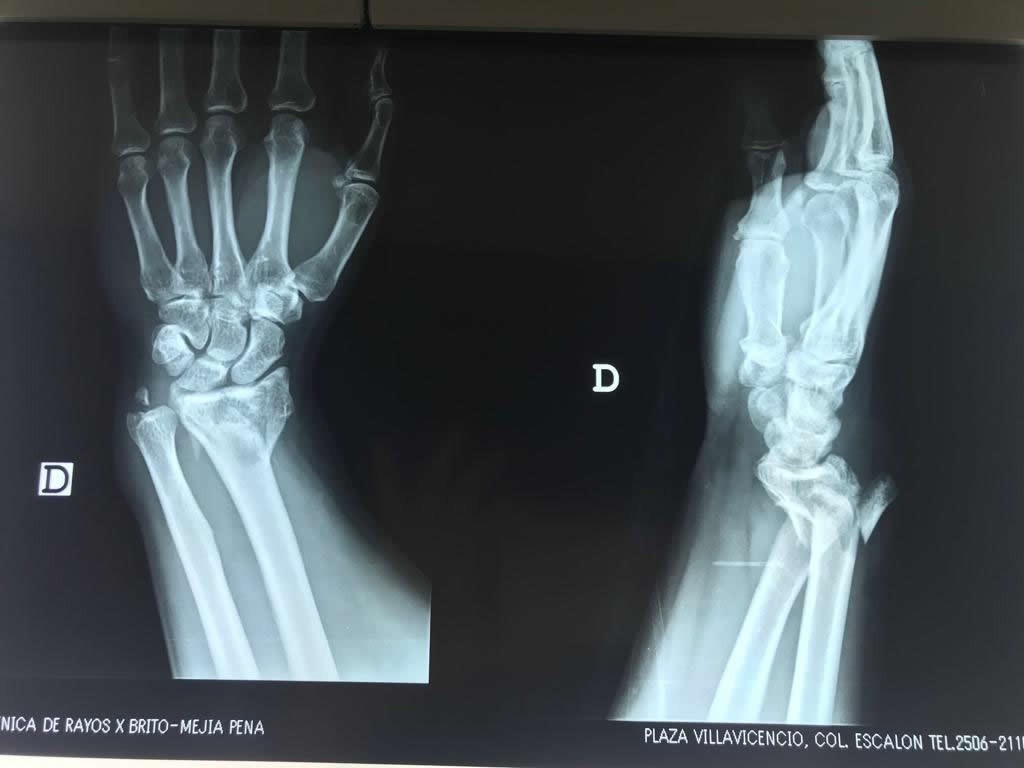

Cirugía de Muñeca y Mano

Los procedimientos más comunes en cirugía de la mano son aquellos destinados a reparar traumatismos, incluyendo lesiones de tendones, nervios, vasos sanguíneos, y articulaciones; huesos fracturados; y quemaduras, cortes, y otros daños de la piel.